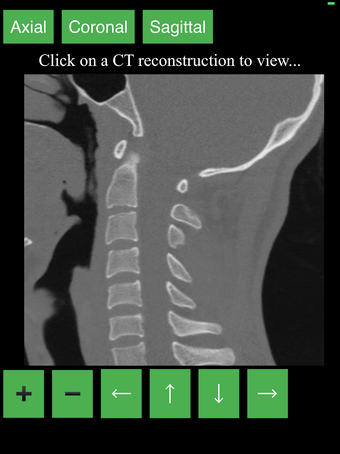

Перекрестные разрезы данных КТ предоставляют динамический и интерактивный метод просмотра поперечной анатомии человека. Вы можете вращать, увеличивать и перемещать изображение, чтобы изучать любую часть тела в деталях.

Перекрестные разрезы создаются с помощью комбинации математических алгоритмов для интерпретации данных из серии сканирований. Результирующие изображения затем преобразуются в серию 2D поперечных срезов и отображаются в специальном приложении для просмотра.